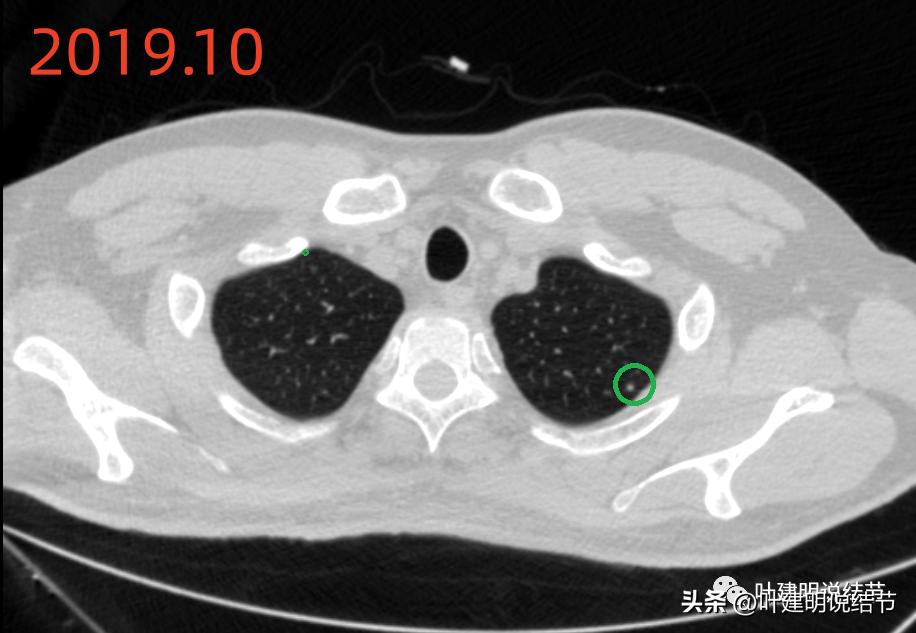

再看2019年时的影像:

当时左上有微小高密度结节(以下称病灶C),考虑良性可能性大。

当时左下有肺炎。